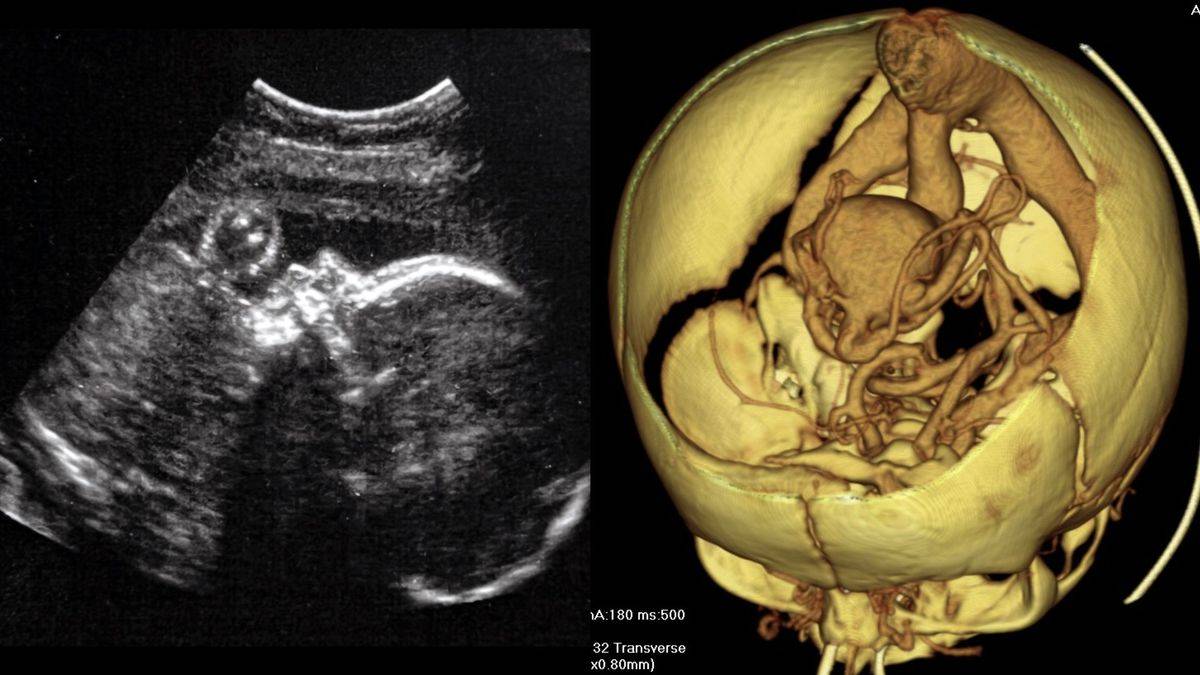

۹. جراحی مغز در رحم:

در یک جراحی نوین، پزشکان توانستند رگ خونی ناهنجار را در مغز جنین را پیش از تولد ترمیم کنند. این ناهنجاری که در حدود ۱ مورد در هر ۶۰ هزار تولد اتفاق میافتد، معمولاً پس از تولد درمان میشود که گاهی بسیار دیر است. در ماه مارس، پزشکان موفق به درمان این ناهنجاری در رحم مادر شدند.